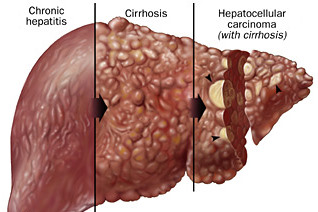

Hepatitis B

- Complications: scarring of the liver, cirrhosis, cancer

- Hepatitis B is a contagious liver disease that ranges in severity from a mild illness lasting a few weeks to a serious, lifelong illness. It results from infection with the Hepatitis B virus. Hepatitis B can be either “acute” or “chronic.”

- Acute Hepatitis B virus infection is a short-term illness that occurs within the first 6 months after someone is exposed to the Hepatitis B virus. Chronic Hepatitis B virus infection is a long-term illness that occurs when the Hepatitis B virus remains in a person’s body.

- 90% of infants who are infected will ultimately develop chronic hepatitis. Only 30% of children age 1-5 develop chronic hepatitis, and only 5-10% of healthy adults who are infected will develop chronic infection.